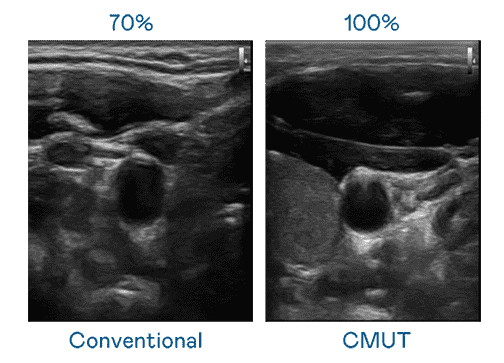

CMUT 技术是一种用电容式微机电元件来产生超音波讯号的技术。。与传统 PZT 压电式技术相比,,,CMUT 频宽增加 30%,,更宽频的超音波讯号让影像解析度大幅提升,,,是实现高影像品质医疗超音波扫描、、促进精准医疗发展的关键技术。。

大频宽带来超清晰影像

超音波影像的解析度高低,,,,首先取决于探头能发出的讯号频宽。。。。918.COM CMUT 可提供高清晰的超音波讯号,,,,提供高频宽、、、、高灵敏度、、、、影像纹理细节更高的超音波影像,,协助医护人员缩短影像判读时间及利用精准的医疗影像进行诊断。。。。